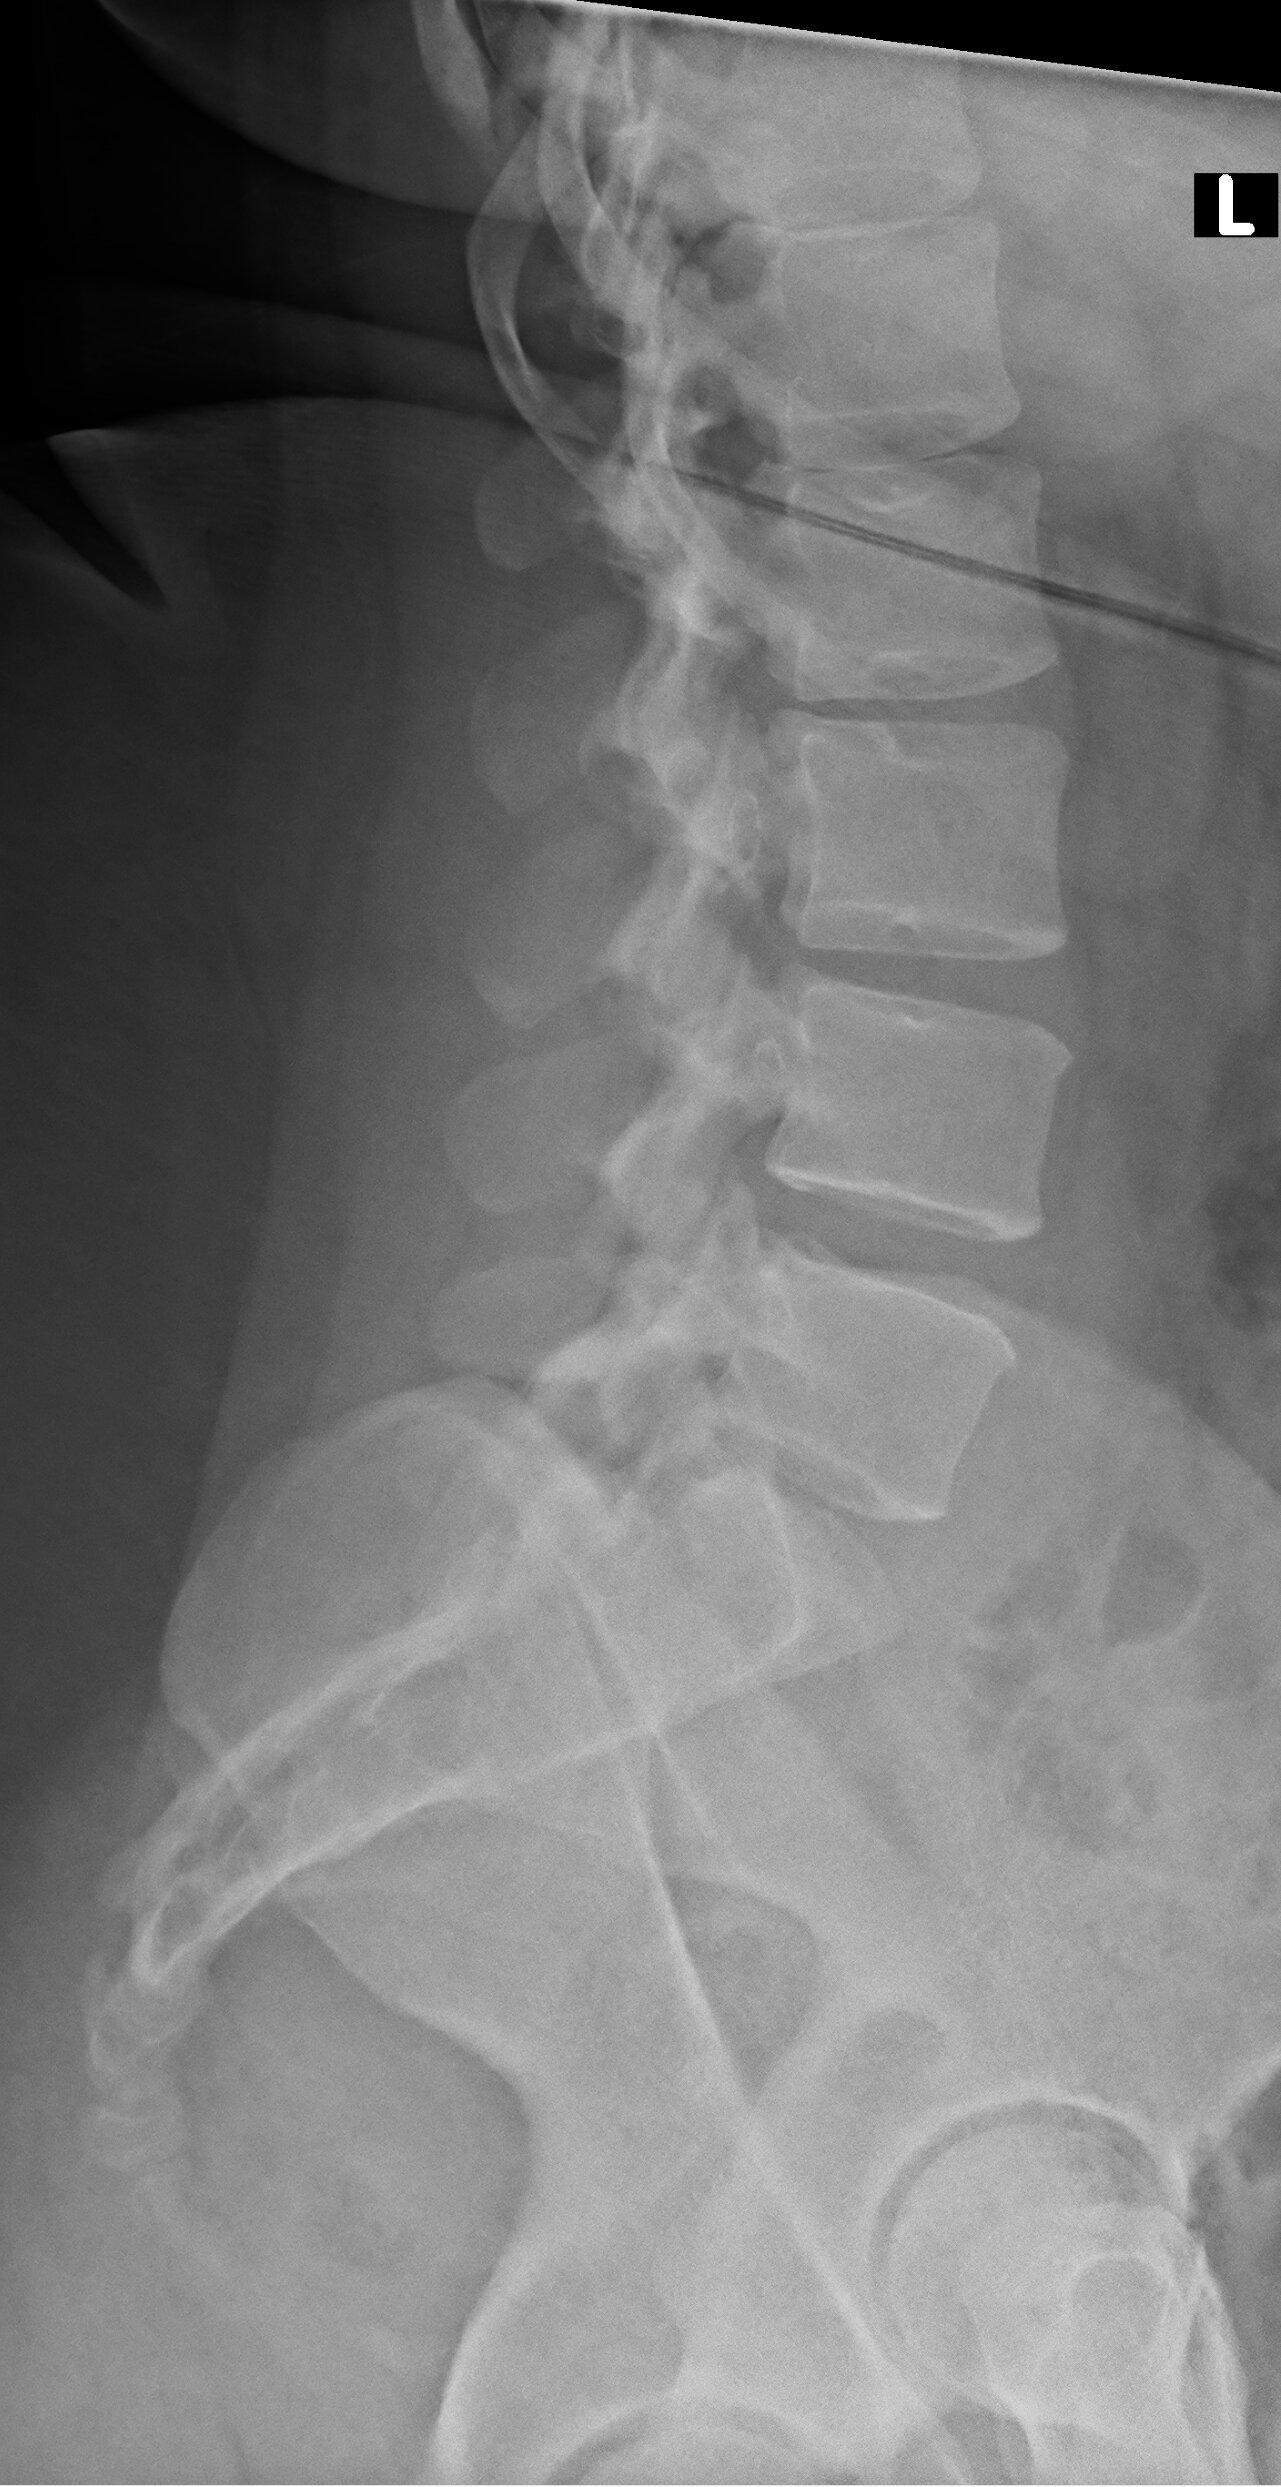

Lws Röntgenbild _ Röntgenbild BWS

Röntgen Lendenwirbelsäule

Röntgen der thorakalen Wirbelsäule (links frontal und rechts lateral): Die Frontalansicht zeigt keine signifikante skoliotische Krümmung, eine normale Wirbelkörperhöhe und eine normal . Dennoch finden die meisten der genannten Kriterien .Bei Rückenschmerzen, die einen Verdacht unterstützen, kommt der bildgebenden Röntgen-Untersuchung eine entscheidende Bedeutung zu: der Mediziner kann sich ein komplettes Bild der Wirbelsäule machen – hier wird meist die Brust- und Lenden-Wirbelsäule (BWS und LWS) untersucht, auch kann das Röntgenbild einen . Lebensjahr in Erscheinung.a, c Deckplattensinterung Lendenwirbelkörper (LWK) 1 mit „vacuum cleft“ (Röntgen) bzw.

Auf dem Röntgenbild einer lumbalen Wirbelsäule ist eine zu mehr als 50 % kollabierte Bandscheibe mit sehr geringem Flüssigkeitsanteil dargestellt (gelber Kreis).